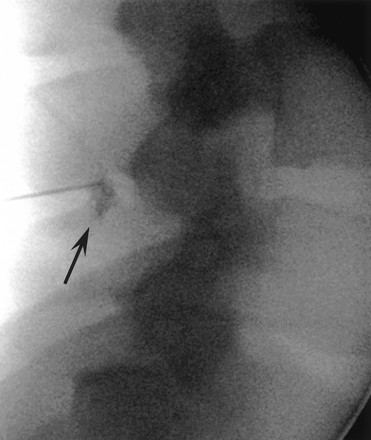

Lateral fluoroscopic images of a 23-year-old man with back pain during LESI procedure. Contrast medium injected at point of loss of resistance is seen overlying the spinous process still within the midback soft tissues (arrow). The needle tip was subsequently advanced to the posterior epidural space and confirmed with epidurogram.